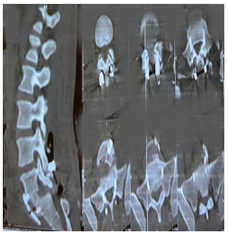

A CT scan of the lumbar spine revealed anterolisthesis of L5 on S1, which was classified as Meyerding grade III with bilateral isthmic lysis of L5 (Figure 1). An angioscan of the iliac vessels was performed to assess the level of bifurcation of the iliac vessels (Figure 2).

Figure 1: CT-Scan of lumbosacral spine in bone window, sagittal reconstruction showing L5 listhesis on S1